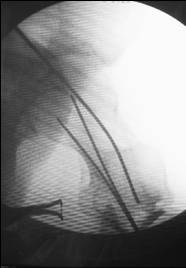

I would use a small wire distractor mentioned in the list some times. Proximal wire is in the iliac crest in AP direction. The leg is adducted. I attached some images. At the AP view under image intensifier you can see adduction but even slight valgus reduction.